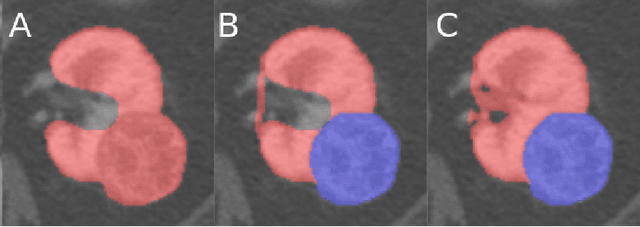

Abstract:There is a large body of literature linking anatomic and geometric characteristics of kidney tumors to perioperative and oncologic outcomes. Semantic segmentation of these tumors and their host kidneys is a promising tool for quantitatively characterizing these lesions, but its adoption is limited due to the manual effort required to produce high-quality 3D segmentations of these structures. Recently, methods based on deep learning have shown excellent results in automatic 3D segmentation, but they require large datasets for training, and there remains little consensus on which methods perform best. The 2019 Kidney and Kidney Tumor Segmentation challenge (KiTS19) was a competition held in conjunction with the 2019 International Conference on Medical Image Computing and Computer Assisted Intervention (MICCAI) which sought to address these issues and stimulate progress on this automatic segmentation problem. A training set of 210 cross sectional CT images with kidney tumors was publicly released with corresponding semantic segmentation masks. 106 teams from five continents used this data to develop automated systems to predict the true segmentation masks on a test set of 90 CT images for which the corresponding ground truth segmentations were kept private. These predictions were scored and ranked according to their average So rensen-Dice coefficient between the kidney and tumor across all 90 cases. The winning team achieved a Dice of 0.974 for kidney and 0.851 for tumor, approaching the inter-annotator performance on kidney (0.983) but falling short on tumor (0.923). This challenge has now entered an "open leaderboard" phase where it serves as a challenging benchmark in 3D semantic segmentation.

Abstract:The morphometry of a kidney tumor revealed by contrast-enhanced Computed Tomography (CT) imaging is an important factor in clinical decision making surrounding the lesion's diagnosis and treatment. Quantitative study of the relationship between kidney tumor morphology and clinical outcomes is difficult due to data scarcity and the laborious nature of manually quantifying imaging predictors. Automatic semantic segmentation of kidneys and kidney tumors is a promising tool towards automatically quantifying a wide array of morphometric features, but no sizeable annotated dataset is currently available to train models for this task. We present the KiTS19 challenge dataset: A collection of multi-phase CT imaging, segmentation masks, and comprehensive clinical outcomes for 300 patients who underwent nephrectomy for kidney tumors at our center between 2010 and 2018. 210 (70%) of these patients were selected at random as the training set for the 2019 MICCAI KiTS Kidney Tumor Segmentation Challenge and have been released publicly. With the presence of clinical context and surgical outcomes, this data can serve not only for benchmarking semantic segmentation models, but also for developing and studying biomarkers which make use of the imaging and semantic segmentation masks.